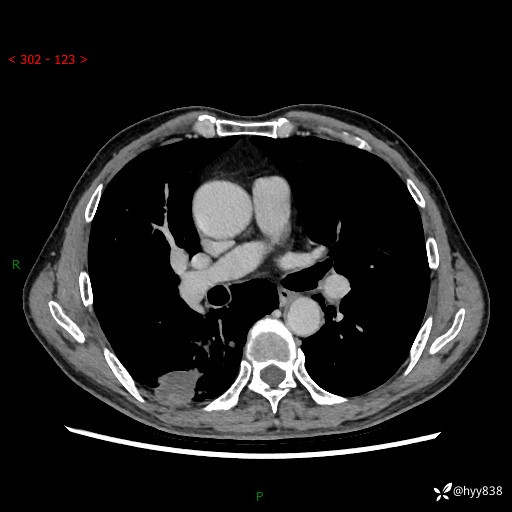

辅助检查:CT

胸部CT平扫

增强